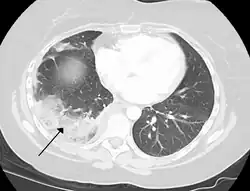

Infarction of the lung due to a pulmonary embolism